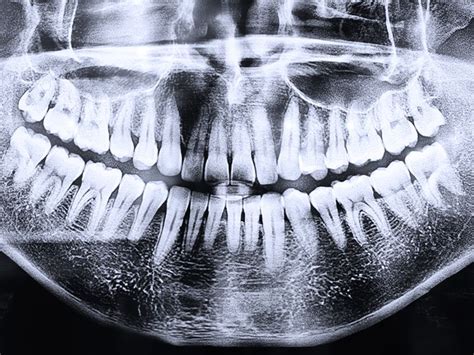

Diagnóstico y Detección

Un dentista puede detectar un canino alto con una simple revisión visual. No es solo una cuestión estética. Los caninos tienen una función clave en la mordida, ya que guían el movimiento lateral de la mandíbula.

Cuanto antes se detecte, mejor. A partir de los 9 años se pueden hacer radiografías para controlar la erupción de los caninos. Si a los 12 no han salido o están fuera de lugar, conviene actuar. Hay que atender a que los caninos altos no siempre duelen. Algunos pacientes sienten molestias cuando el diente empuja desde el interior.